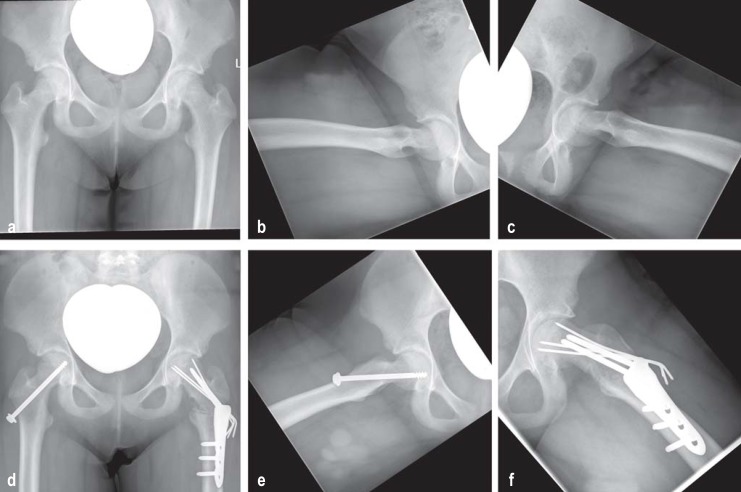

Figure 2.

Radiographic diagnosis of slipped capital femoral epiphysis and its surgical management, showing the time course

a) Preoperative anteroposterior (AP) pelvic radiograph; b) Preoperative true lateral view of the right hip;

c) Preoperative true lateral view of the left hip; (pathological: slippage >50°);

d) Postoperative AP pelvic radiograph after prophylactic in situ screw placement (right hip) and valgization–flexion–derotation osteotomy (Weber–Imhäuser osteotomy) (left hip);

e) Postoperative axial view of the right hip with prophylactic in situ screw placement

f) Postoperative axial view of the left hip with valgization–flexion–derotation osteotomy (Weber–Imhäuser osteotomy)

The pathophysiology of this nontraumatic epiphysiolysis in adolescents is multifactorial. Boys are somewhat more frequently affected than girls. There appears to be a correlation between hormones, obesity, and high mechanical load. Clinically, an acute form (symptoms <2 weeks) and a chronic form of the disease (symptoms >2 weeks) are distinguished. A special form is the “acute on chronic” form, in which a sudden increase in pain occurs in a patient with a longstanding positive history. Often, the patient reports localized pain in the knee but examination reveals painful reduced mobility of the hip (especially in internal rotation) in a patient in otherwise good health (26). A positive Drehmann sign on the affected side (where the examiner notes unavoidable passive external rotation of the hip—i.e., internal rotation of the lower leg—when the hip joint is flexed) is pathognomonic. The natural course of the disease is for the symptoms to gradually disappear spontaneously, and as a result diagnosis is often delayed (27). In cases where slipped capital femoral epiphysis (SCFE) is suspected, the next diagnostic step should be radiography in two planes (AP pelvic view and Lauenstein axial view of the affected side). MRI does not have a role in the diagnostic procedure in the early stage of SCFE (4). Surgical treatment depends on the angle of slip of the femoral head from the femoral neck. In German-speaking countries, where the angle of slip is up to 30°, “in situ screw fixation” using one screw or three K wires is carried out to prevent further slipping of the growth plate. Where the angle of slip is greater than 30°, a pre-arthritic deformity is present, so reshaping osteotomies are performed in addition (figure 2). Finally, surgical hip dislocation with open reduction and fixation of the epiphysis (periacetabular osteotomy) and modified Dunn osteotomy are becoming more widely practiced. Complication rates of up to 37% are reported for these procedures; the rate of femoral head necrosis is reported at 23%, and there is a significant correlation between complication rate and surgical expertise (28). SCFE should always be treated surgically; the acute form should be treated emergently and the chronic form within a short time. Since in 50% of cases slipping will at some time occur in the normal hip as well, prophylactic screw placement on the contralateral side is recommended.